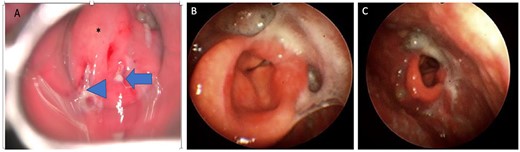

(A) Direct laryngoscopic examination shows a swollen epiglottis (*) with pus extruding at the level of the right and left aryepiglottic folds as indicated by arrowhead and arrow, respectively. (B) Transnasal laryngoscopic examination of the larynx at Day 7 post-operatively revealed a normal-shaped epiglottis (*) with a visible glottic airway during adduction and (C) abduction.

A 72-year-old man with diabetes presented to the emergency department with dyspnea, stridor and odynophagia that suddenly started 3 h earlier. Clinical examination revealed that the patient was febrile with hypoxia, hoarseness and drooling. Flexible fiber optic rhinopharyngo-laryngoscopy showed pooling of secretions in the pyriform sinuses, a swollen and edematous epiglottis, poor visualization of the glottis and reduced vocal cord movement. A lateral neck radiograph revealed a swollen epiglottis and, due to his respiratory distress, the patient was intubated by the emergency physician in the emergency room; CT of the neck with intravenous contrast revealed a multiloculated abscess involving the epiglottis, and paraglottic as well as parapharyngeal spaces (Fig. 1A and B). Laboratory workup revealed an elevated white blood cell count and inflammatory markers. The patient was transferred to the operating room for microlaryngoscopic examination, combined transoral and transcervical incision, neck abscess drainage and tracheostomy. A Klinssaer laryngoscope was used to expose the supraglottic and glottic regions. A gush of pus was observed during laryngoscope insertion into the vallecula and epiglottis, and two small incisions were made at the level of the ventricular folds using a laryngeal knife (Fig. 2A). A swab was collected and sent for bacteriological and mycological examination. The tissue biopsies were performed using cup forceps. Subsequently, a transcervical approach to drain the left parapharyngeal space was begun, with an incision made two fingerbreadths below the left mandible, after which the subplatysmal flaps were elevated superiorly and inferiorly. The parapharyngeal space was accessed after medial retraction of the submandibular gland and dissection above the posterior belly of the digastric muscle, where pus collection was drained. Warm saline irrigation in addition to diathermy was used to achieve hemostasis, and a negative pressure drain system was inserted prior to multilayer wound closure. Finally, a tracheostomy was performed utilizing a 2-cm anterior neck incision at the level of the third tracheal ring. At the end of the procedure, a nasogastric tube was inserted to ensure enteral feeding during the recovery period. After an infectious disease consultation, the patient was started on ceftriaxone and metronidazole for 1 week. Marked improvement in the patient’s symptoms was observed. The flexible scope showed improved visualization and mobility of the supraglottic and glottic areas (Fig. 2B and C), and decannulation was performed on day 4 after passing a trial. A CT scan repeated 1 week post-operatively revealed marked resolution of the abscess (Fig. 1C). The patient was administered oral antibiotics for another week. Clinical follow-up after 1 month was unremarkable.